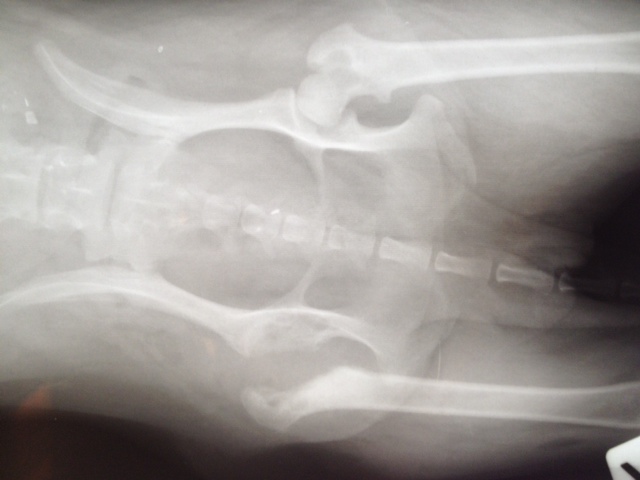

Also hatte Felipa heute (01.08.) ihre 2.OP - allerdings wie gesagt ganz anders als geplant. Der Chirurg entfernte den kaputten Knorpel, wie man auch als Laie an den Aufnahmen gut erkennen kann.